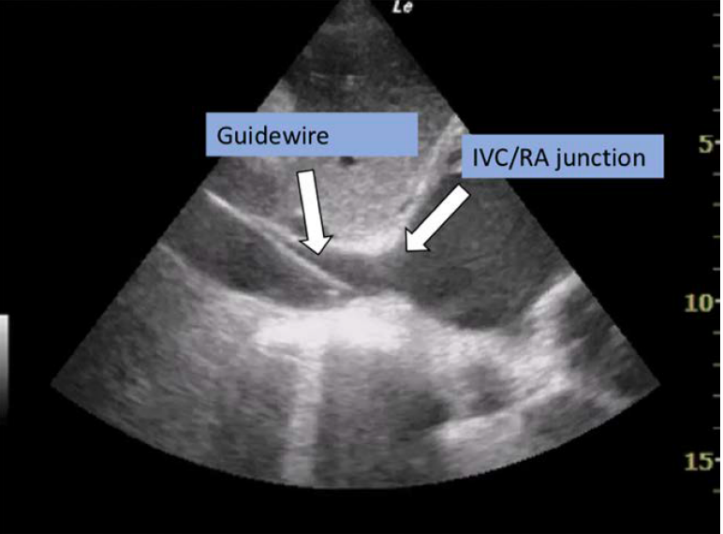

在给予足够抗凝治疗后,在相应的血管中置入标准导丝,并进行逐步扩张以便于置入插管。在某些情况下,如肥胖、解剖结构扭曲和周围血管疾病,可能需要硬导丝支撑,然后将插管分别置入股动脉和静脉。推荐使用影像(超声,x线透视或x线片)来确认导丝的初始位置,引引导丝前进,并确认动脉和静脉插管的位置(见图5和图6)。标准x线胸片足以确认准确置入后的插管位置。

图6: 剑突下心脏超声心动图显示导丝在IVC/RA交界处。IVC,下腔静脉; RA,右心房。